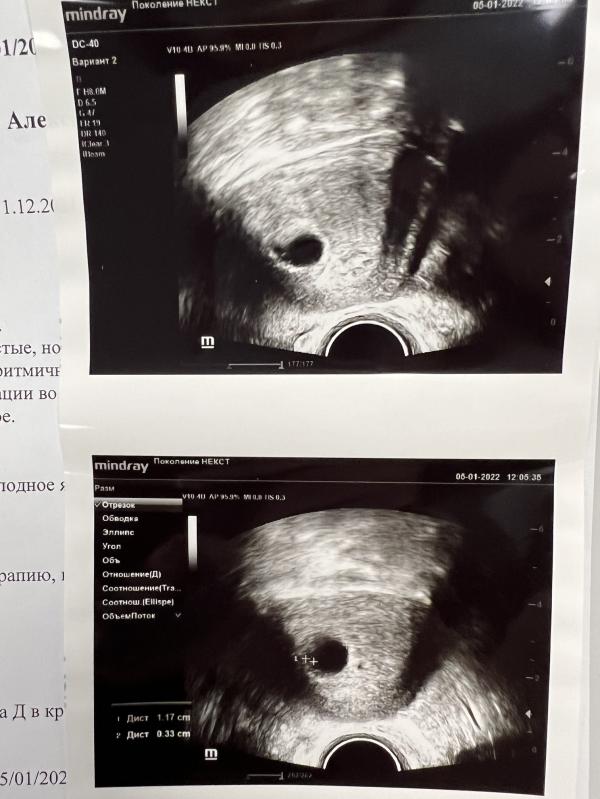

05.01.2022 была на подтверждающем УЗИ🤗

@v.tatzenko2018, только плодное яйцо,надо было удостовериться что он в матке